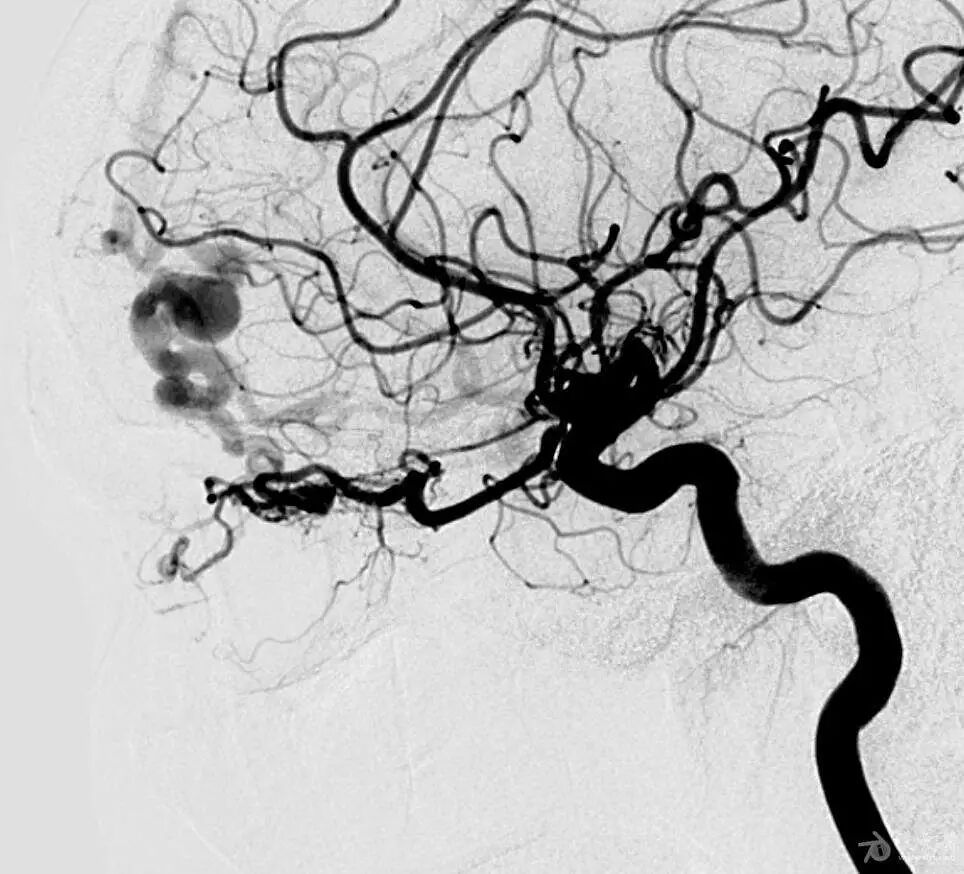

硬脑膜动静脉瘘(DAVF)是一种少见的脑血管畸形,占所有颅内血管畸形的10%-15%。

硬脑膜动静脉瘘,其实质是发生在“硬脑膜”及其附属结构上的“动静脉瘘”。动静脉瘘则是动脉血管和静脉血管之间的直接短路,可先天存在或因后天各种因素导致。

症状表现多样化,这与其静脉引流的多样性有关,静脉引流的方式决定了临床表现的轻重和患者的预后。有些可以仅表现为轻微的头痛耳鸣症状,亦可表现为致命的脑出血。其中颅内杂音、颅内出血和眼部症状最常见,脑出血和神经功能障碍最为严重,表现为颅内出血的患者,两周内再出血的风险可高达35%。

介入治疗适合绝大多数患者,效果好。指征:①单根皮质引流静脉,特别是引流静脉已有迂曲,呈动脉瘤样扩张,需立即治疗,防止破裂出血;②有颅内出血史;③颅内压增高,视盘水肿,影响视力者;④局灶性神经功能障碍,进行性加重;⑤影响生活的头痛和颅内杂音。包括静脉入路与动脉入路,静脉入路包括眼静脉和静脉窦入路。动静脉联合入路主要用于多瘘口复杂的瘘,有时需要多次进行。